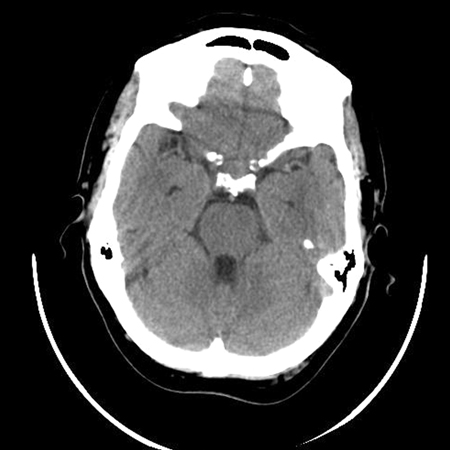

- Pituitary apoplexy

- Cerebral aneurysm